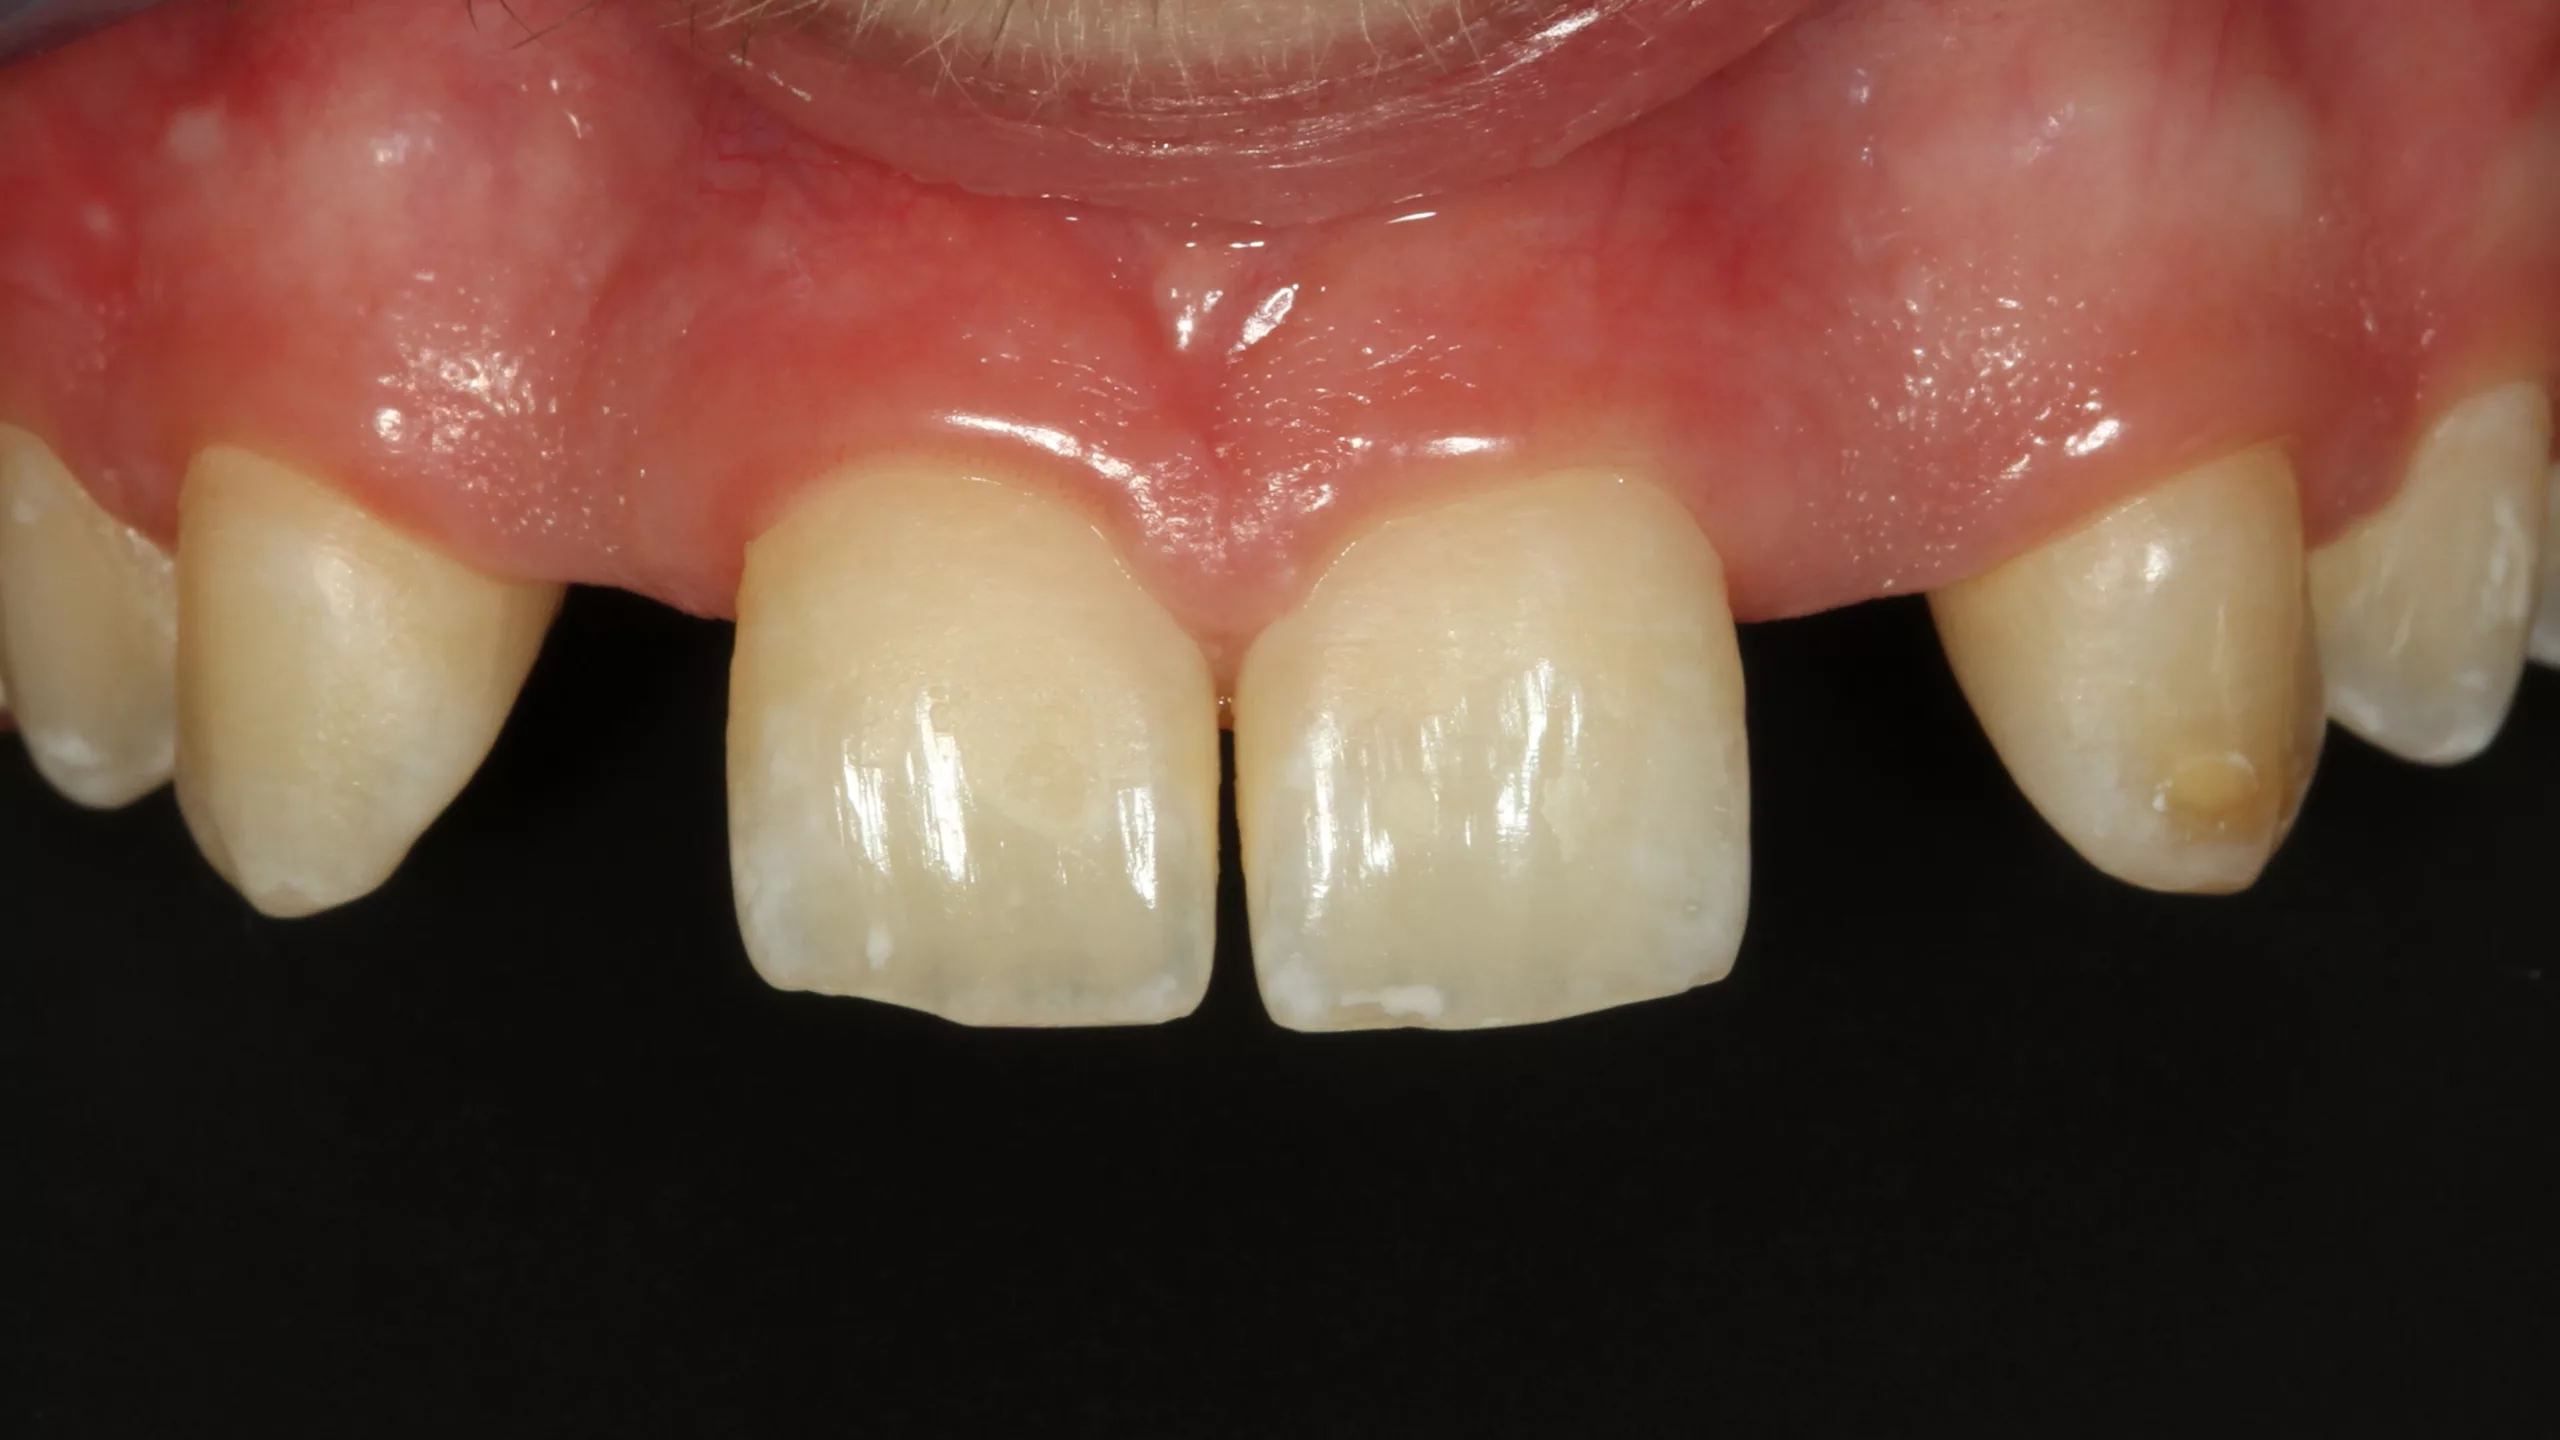

Bei der 55-jährigen Patientin bestand der Wunsch nach einer ästhetischen Neuversorgung ihrer Frontzahnsituation (Abb. 29 und 30). Die Zähne 11 und 22 waren wurzelkanalbehandelt, alle Schneidezähne wiesen ältere, große, farblich nicht mehr passende Kompositversorgungen auf. Die Neuversorgung wurde aufgrund der Stabilität und der besseren Abdeckung verfärbter Zahnbereiche aus einem monolithischen Zirkonmaterial gefertigt, die labial additiv verblendet wurden (Abb. 31 und 32).